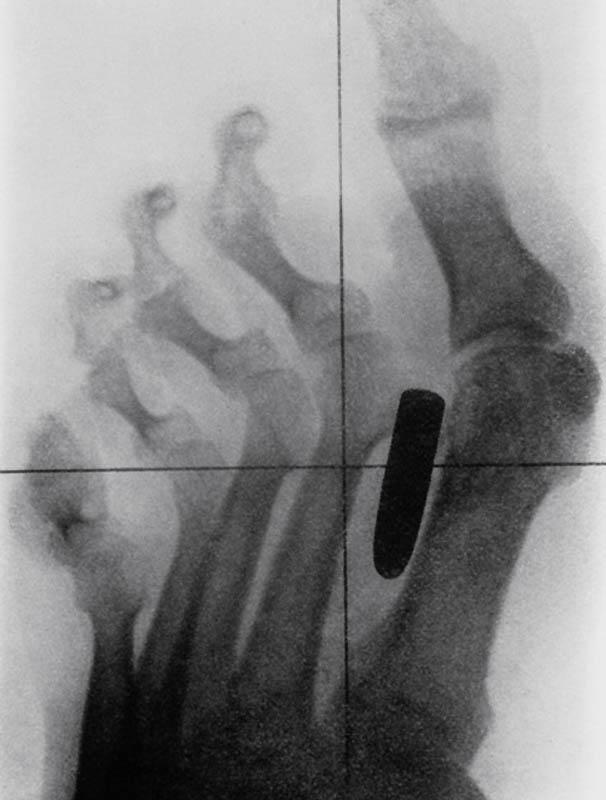

Пуля застряла в плюсневой кости между большим и вторым пальцами.